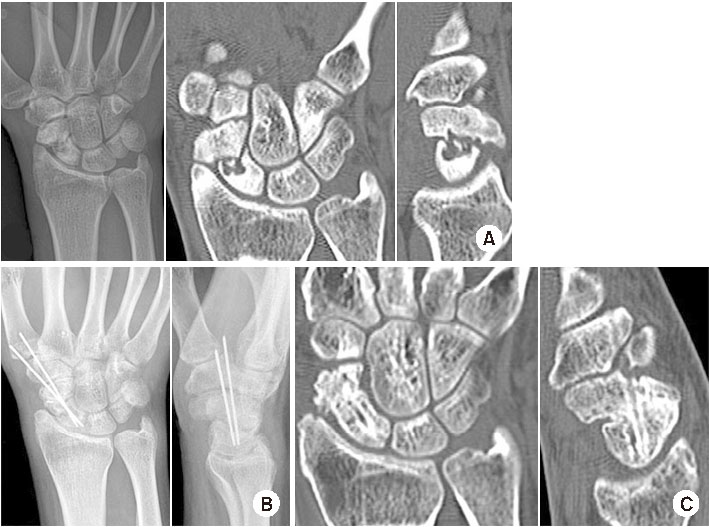

비혈관화 골이식은 가장 흔하게 쓰이는 방법이며 주로 자가 장골(autogenous iliac bone)이나 자가 원위 요골을 사용한다. Matti-Russe 술식15)과 Fernandez 술식36)이 가장 고전적인 방법으로 이것을 변형한 다양한 술식들이 쓰인다. Matti-Russe 술식은 수장측 접근으로 불유합 부위를 노출한 뒤 소파술을 시행하여 근위 및 원위 골편 안에 공간을 만들고 이곳에 막대 형태의 피질-해면골을 이식하는 방법이다. Fernandez 술식은 소파술 후 쐐기 형태의 피질-해면골을 이식하여 주상골의 굴곡 변형을 교정하는 방법이다. 불유합 부위의 골경화(sclerosis)와 낭종(bone cystic)은 소파술로 제거한다. 소파술은 점상 출혈이 확인될 때까지 충분히 시행하는 것이 좋다. 골이식 후에는 유관 나사나 K-강선으로 고정한다(Fig. 2). 유관 나사로 좀 더 견고한 고정을 할 수 있으나 근위골편이 작아서 충분히 관통하지 못하는 경우는 K-강선으로 고정한다.37) 주상골 허리 부위보다 원위부의 불유합은 대부분 이와 같은 비혈관화 골이식으로 좋은 결과를 얻을 수 있다.9) 그러나 무혈성 괴사가 동반될 수 있는 근위극 불유합의 경우는 치료가 어려울 수 있다.

Fig. 2

(A) A 15-year-old male had a scaphoid nonunion in his right wrist, computed tomography showed a severe humpback deformity of the scaphoid. (B) During the operation, the scaphoid waist showed pseudarthrosis. After sufficient curettage, a wedge strut bone graft was placed in the area of pseudarthrosis. (C) A cannulated screw was used for fixation. (D) Lateral radiographs of the right wrist showed a slight recovery of the DISI deformity after surgery.